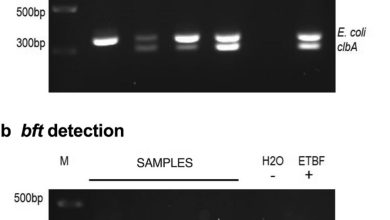

Novos insights sobre câncer colorretal e E. coli

detecção de clbA e bft. a presença de a clbA e b bft em DNA extraído de amostras fecais foi…